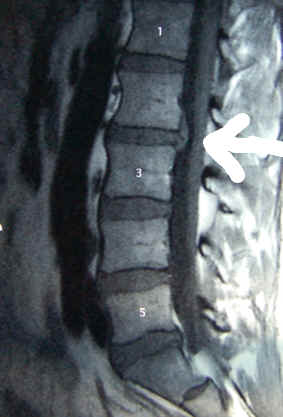

Am zweiten Apriltag sollte eigentlich in Großenseebach die Halbmarathonbestzeit

wackeln. Es war relativ warm und es war windig, aber der Grund dafür, dass ich nicht dort war, liegt woanders und zwar genau zwischen zwei Lendenwirbeln. Was das genau bedeutet, wird mir Stephan am Montag wohl

genauer erzählen…

Die gute Nachricht: mit dem Knie und mit der Hüfte ist alles in Ordnung. Die schlechte Nachricht: die Bandscheibe macht Probleme und daher resultierten auch die Schmezen im linken Bein. Weitere Klarheit

wird nun die Kernspin am 31.03. verschaffen, es besteht Verdacht auf Bandscheibenvorfall. Bis dahin müssen Massagen und Fangopackungen helfen. Nun muss sich nur noch die Zeit dafür finden. Am 14.

März ging wohl eine hoffnungsvolle Saison zu Ende...